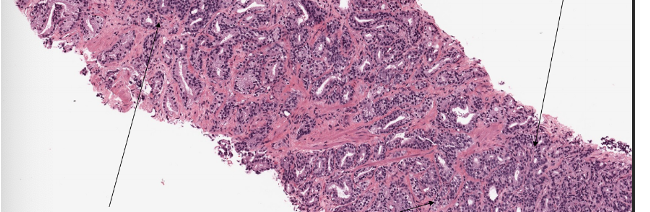

What is this?

Prostatic cancer

What are the grades shown at different locations?

What is seen in prostate carcinoma?